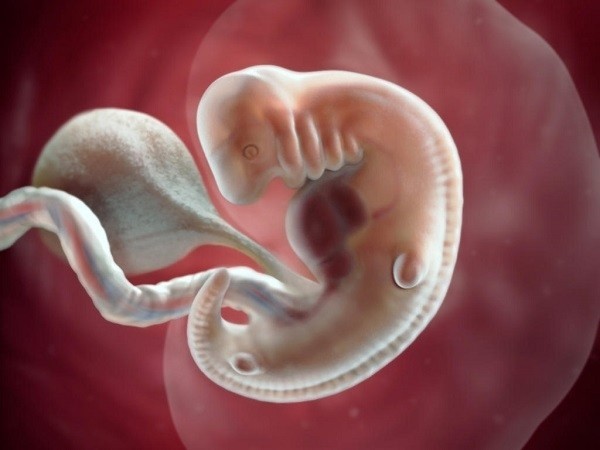

Sự phát triển của thai nhi tuần 7

Từ tuần 7 thì con đã chớm hình thành các đầu ngón tay, ngón chân có màng, phần đuôi mở rộng của xương cụt cũng dần biến mất. Hệ thần kinh đã bắt đầu phân nhánh, tạo thành hệ sơ khai. Con đã dần xuất hiện mí mắt và cả ống thở kéo dài từ cổ họng đến nội tạng phổi.

Sự phát triển của thai nhi ở tuần 7

Kích thước phát triển của con trong tuần thứ 7. Kích thước chuẩn cho thai nhi vào tuần 7 là cân nặng khoảng 1gr, chiều dài từ 5-12 mm. Số đo khá nhỏ nên nhìn từ bên ngoài, mẹ sẽ không có sự thay đổi rõ rệt về cơ thể.